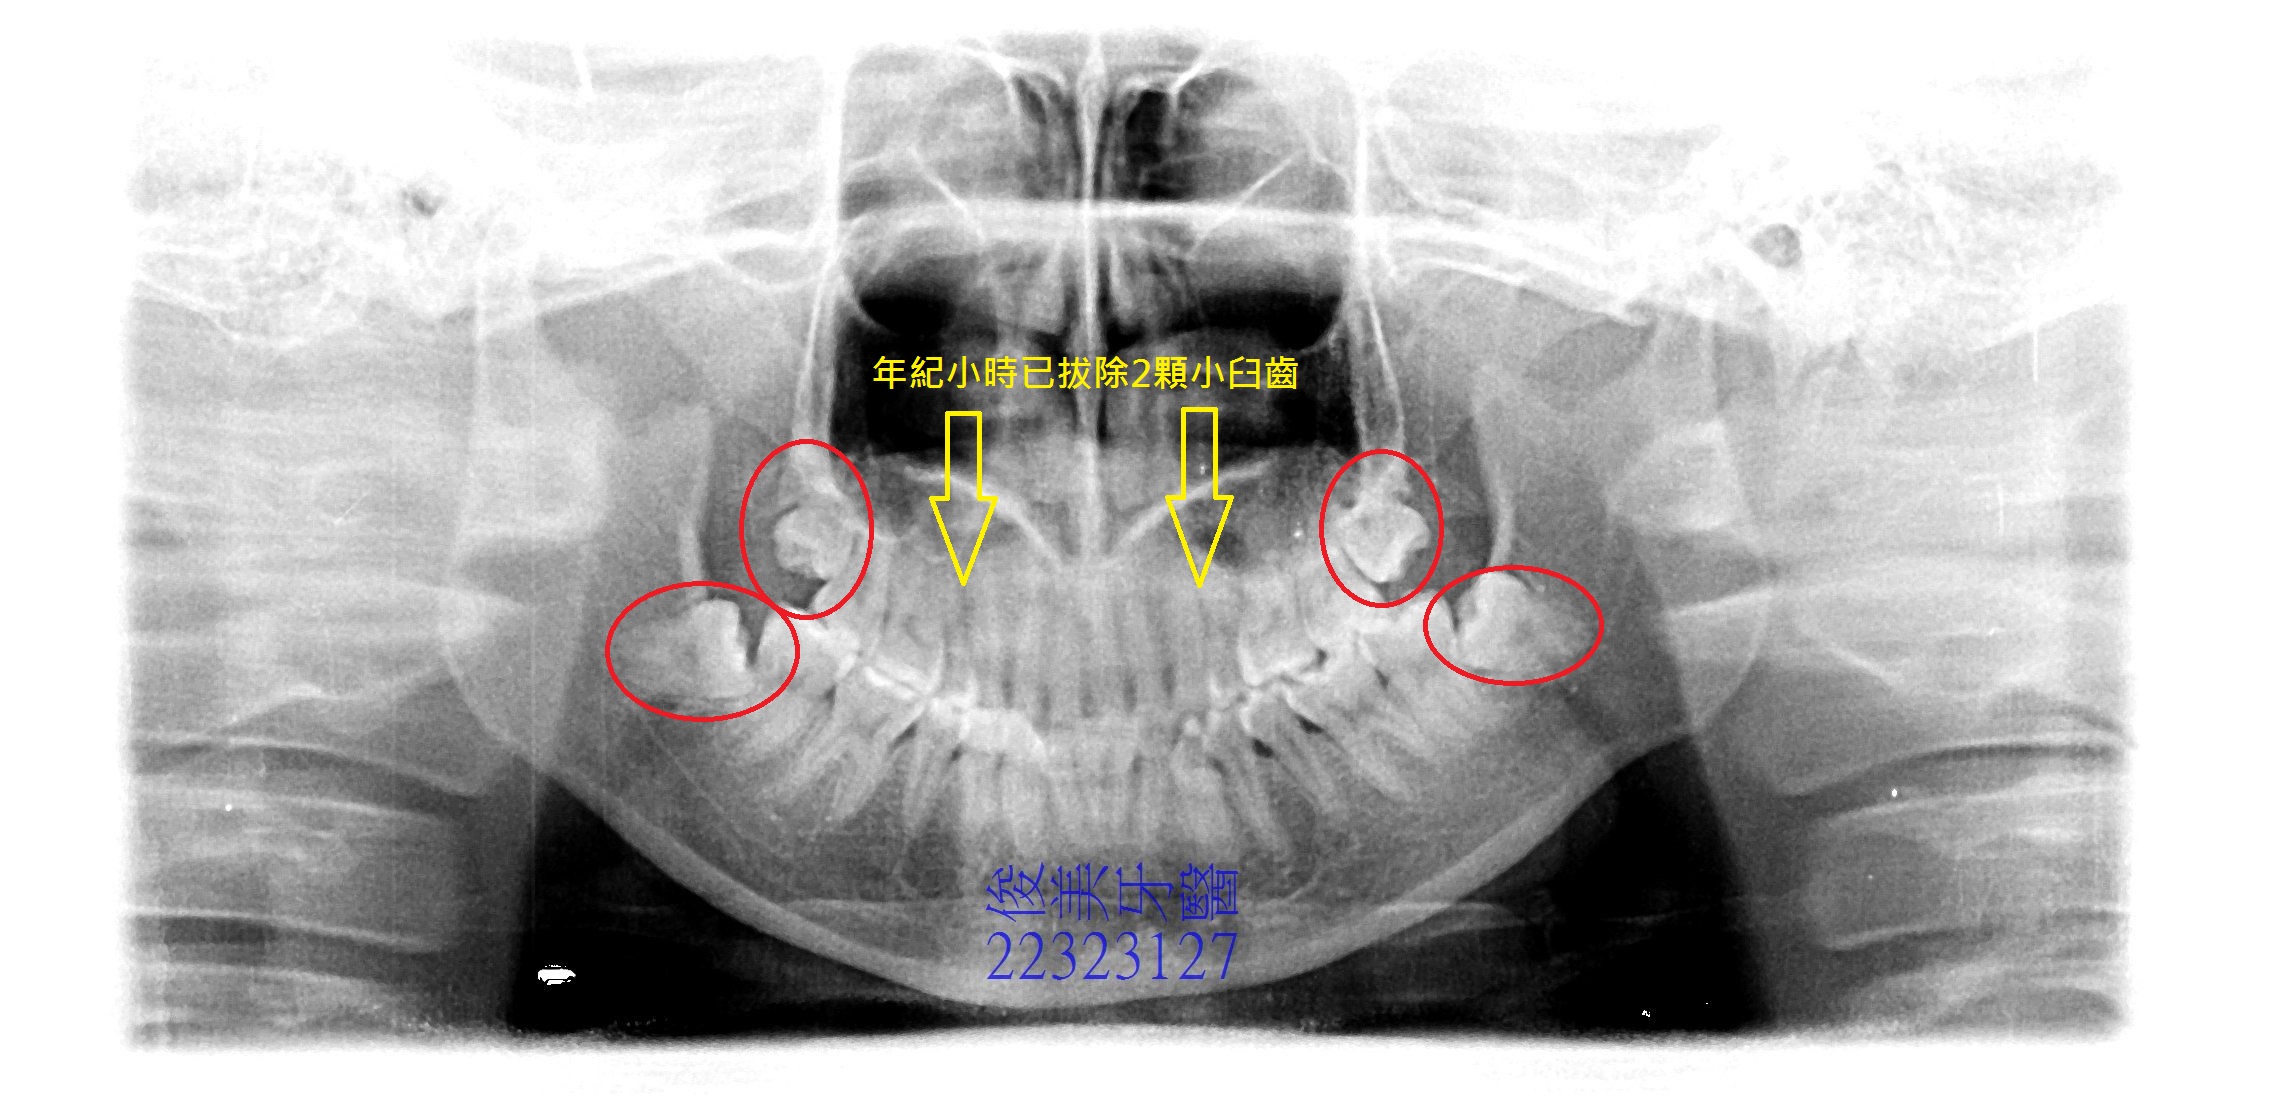

患者因小時侯曾想做矯正治療,拔除了2顆上顎小臼齒,但後來不知何因素沒有完整治療,因此於18歲後智齒干擾也未做處理,導致牙齒歪斜的愈來愈嚴重。想要改善,在諮詢後已有心理準備。

陸續將4顆智齒拔除後,安排進入療程。

原先醫師規畫將患者上顎小臼齒空間挪移出來,要修復回去,後考量患者骨架確實不大,空間不足以多放兩顆小臼齒,因此只將牙齒排列好,並調整全口咬合高度及受力點做重分配,加上設計患者的前牙美觀,讓患者變身成為精緻女孩。